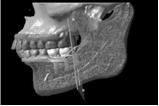

白黒の立体画像では骨の高さや厚みと、神経の出口、歯の形などが分かりますが、

神経がどんな走行をしているかはわかりません。

そこで、詳しく骨の中の状態を見るためにはCTデータ3D立体構築画像変換検査をしていきます。

この検査によって3次元的に対象部の形態や位置関係をさらに詳しく知ることができます。

これは骨が溶けて神経が露出している状態です

この検査によりどこに重要な神経が通っているか一目瞭然です。